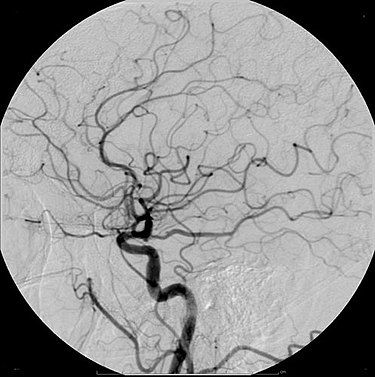

Ett litet pytteexempel – som i och för sig själv kan utvecklas till något synnerligen besvärande – på oförutsedda konsekvenser gäller kontrastmedel. ”Kontrastmedel eller kontrastmedium”, förklarar Wikipedia, ”är ett ämne som används för att öka kontrasten hos strukturer eller vätskor i kroppen vid medicinsk avbildning”. Det handlar om medicinsk färgsättning som gör att läkare bättre kan se på röntgenbilder vad som verkligen händer vid en hjärnblödning, hjärtattack eller lungproppar (se bilden).